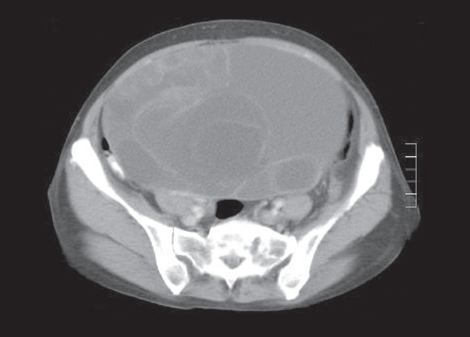

discitis

David Effron, MD; Maya C. Myslenski, MD

A 25-month-old white female presented with a 1.5-week history of intermittent, cramping, diffuse abdominal pain, increasing irritability, and decreased activity.